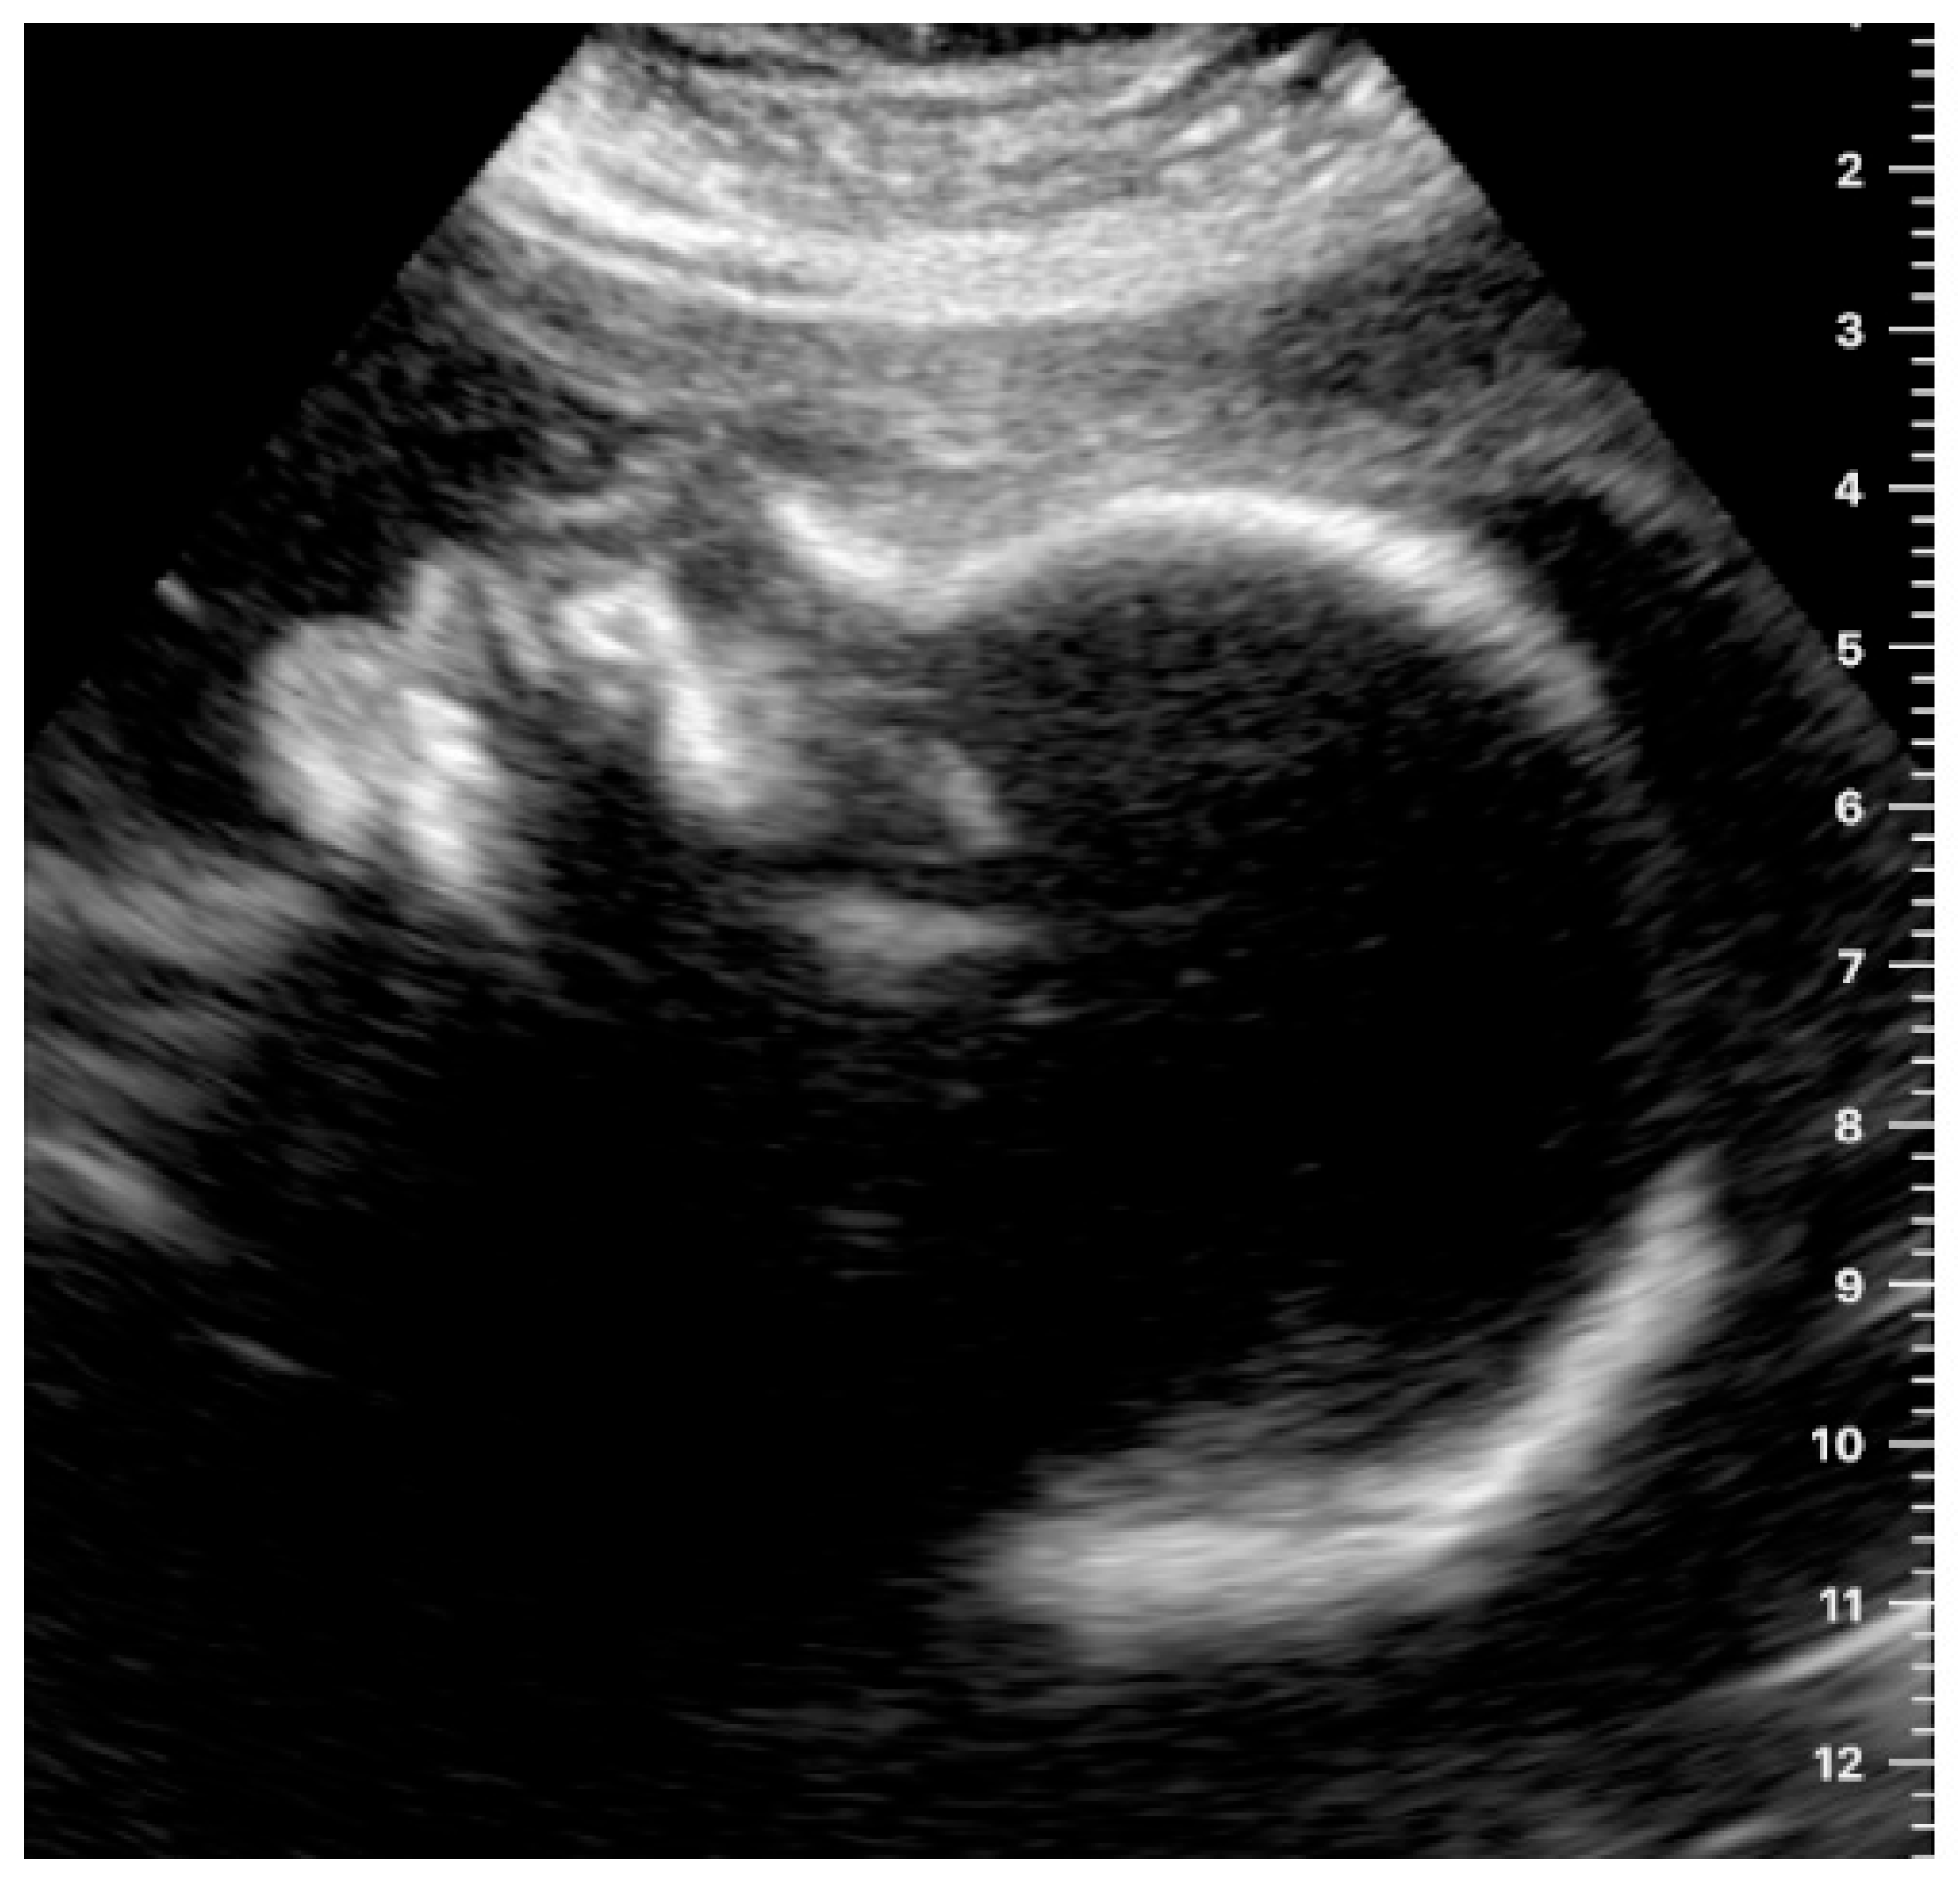

The fetal profile was located satisfactorily by 14.3% of the women in still images (an example is shown in Figure 4) and by 17.9% in the videos.

Figure 4.

Example of an image obtained by a study participant, showing the fetal profile (satisfactory presentation).